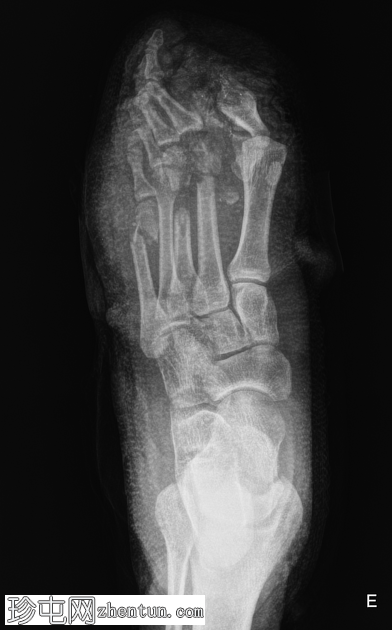

X线片

斜位

第一跖趾关节脱位。

第二跖骨头粉碎性骨折脱位。

第三跖骨骨折伴节段性骨缺损。

第五跖骨颈移位性骨折。